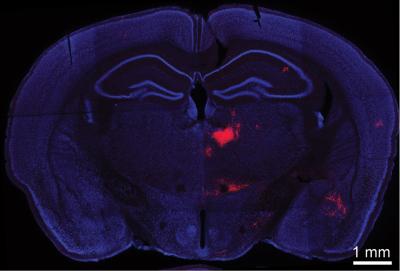

A coronal section of a mouse brain. Bo Li and colleagues induced PV interneurons of the medial prefrontal cortex (mPFC) to produce a red fluorescent marker that illuminates any neurons providing input to them. A direct connection is implied, therefore, with red-labeled neurons seen in this image, located in the mediodorsal thalamus (MD). Li's team has discovered an inhibitory circuit between the two brain areas that when disrupted may underlie cognitive disorders such as schizophrenia.

The thalamus acts as a gateway through which information from other parts of the brain is collected and processed before being sent on to the cortex. This thalamocortical circuit is often fine-tuned by inhibitory neurons, which tamp down signaling between message-propagating excitatory neurons. Li and colleagues focused on connections between sections of the PFC and the thalamus called the medial prefrontal cortex (mPFC) and the mediodorsal thalamus (MD). They observed a process called feedforward inhibition, a mechanism in which one neuron excites a neighboring or "downstream" neuron, but also recruits a third neuron to inhibit the downstream target after some delay.

As described in work published today in The Journal of Neuroscience , Li and his colleagues used optogenetic stimulation, a technique in which neurons expressing a light-sensitive protein are controlled with pulses of light, to activate neurons in the thalamus. These neurons in turn activated two classes of cells in the prefrontal cortex - inhibitory PV interneurons as well as excitatory pyramidal neurons. The relative timing of their activation suggested to Li's team that the inhibitory cells might be shaping the activity of the excitatory ones.. The team now proposes that PV interneurons can dictate the time period during which the pyramidal neurons integrate excitatory input from neurons in the thalamus.